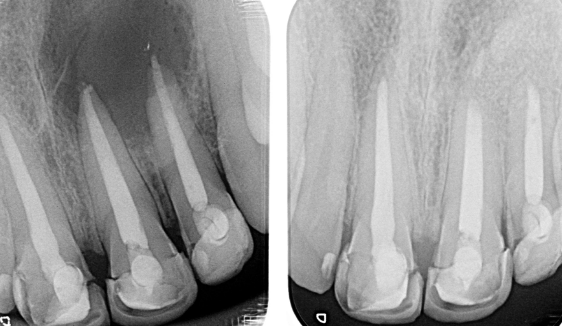

Se hace una incisión en el tejido de las encías para exponer el hueso y el tejido inflamado circundante. El tejido dañado se elimina junto con el extremo de la punta de la raíz. Se coloca un relleno en el extremo de la raíz para evitar la reinfección de la raíz y se sutura la encía.

El hueso se cura de forma natural alrededor de la raíz durante un período de meses restaurando su función por completo.